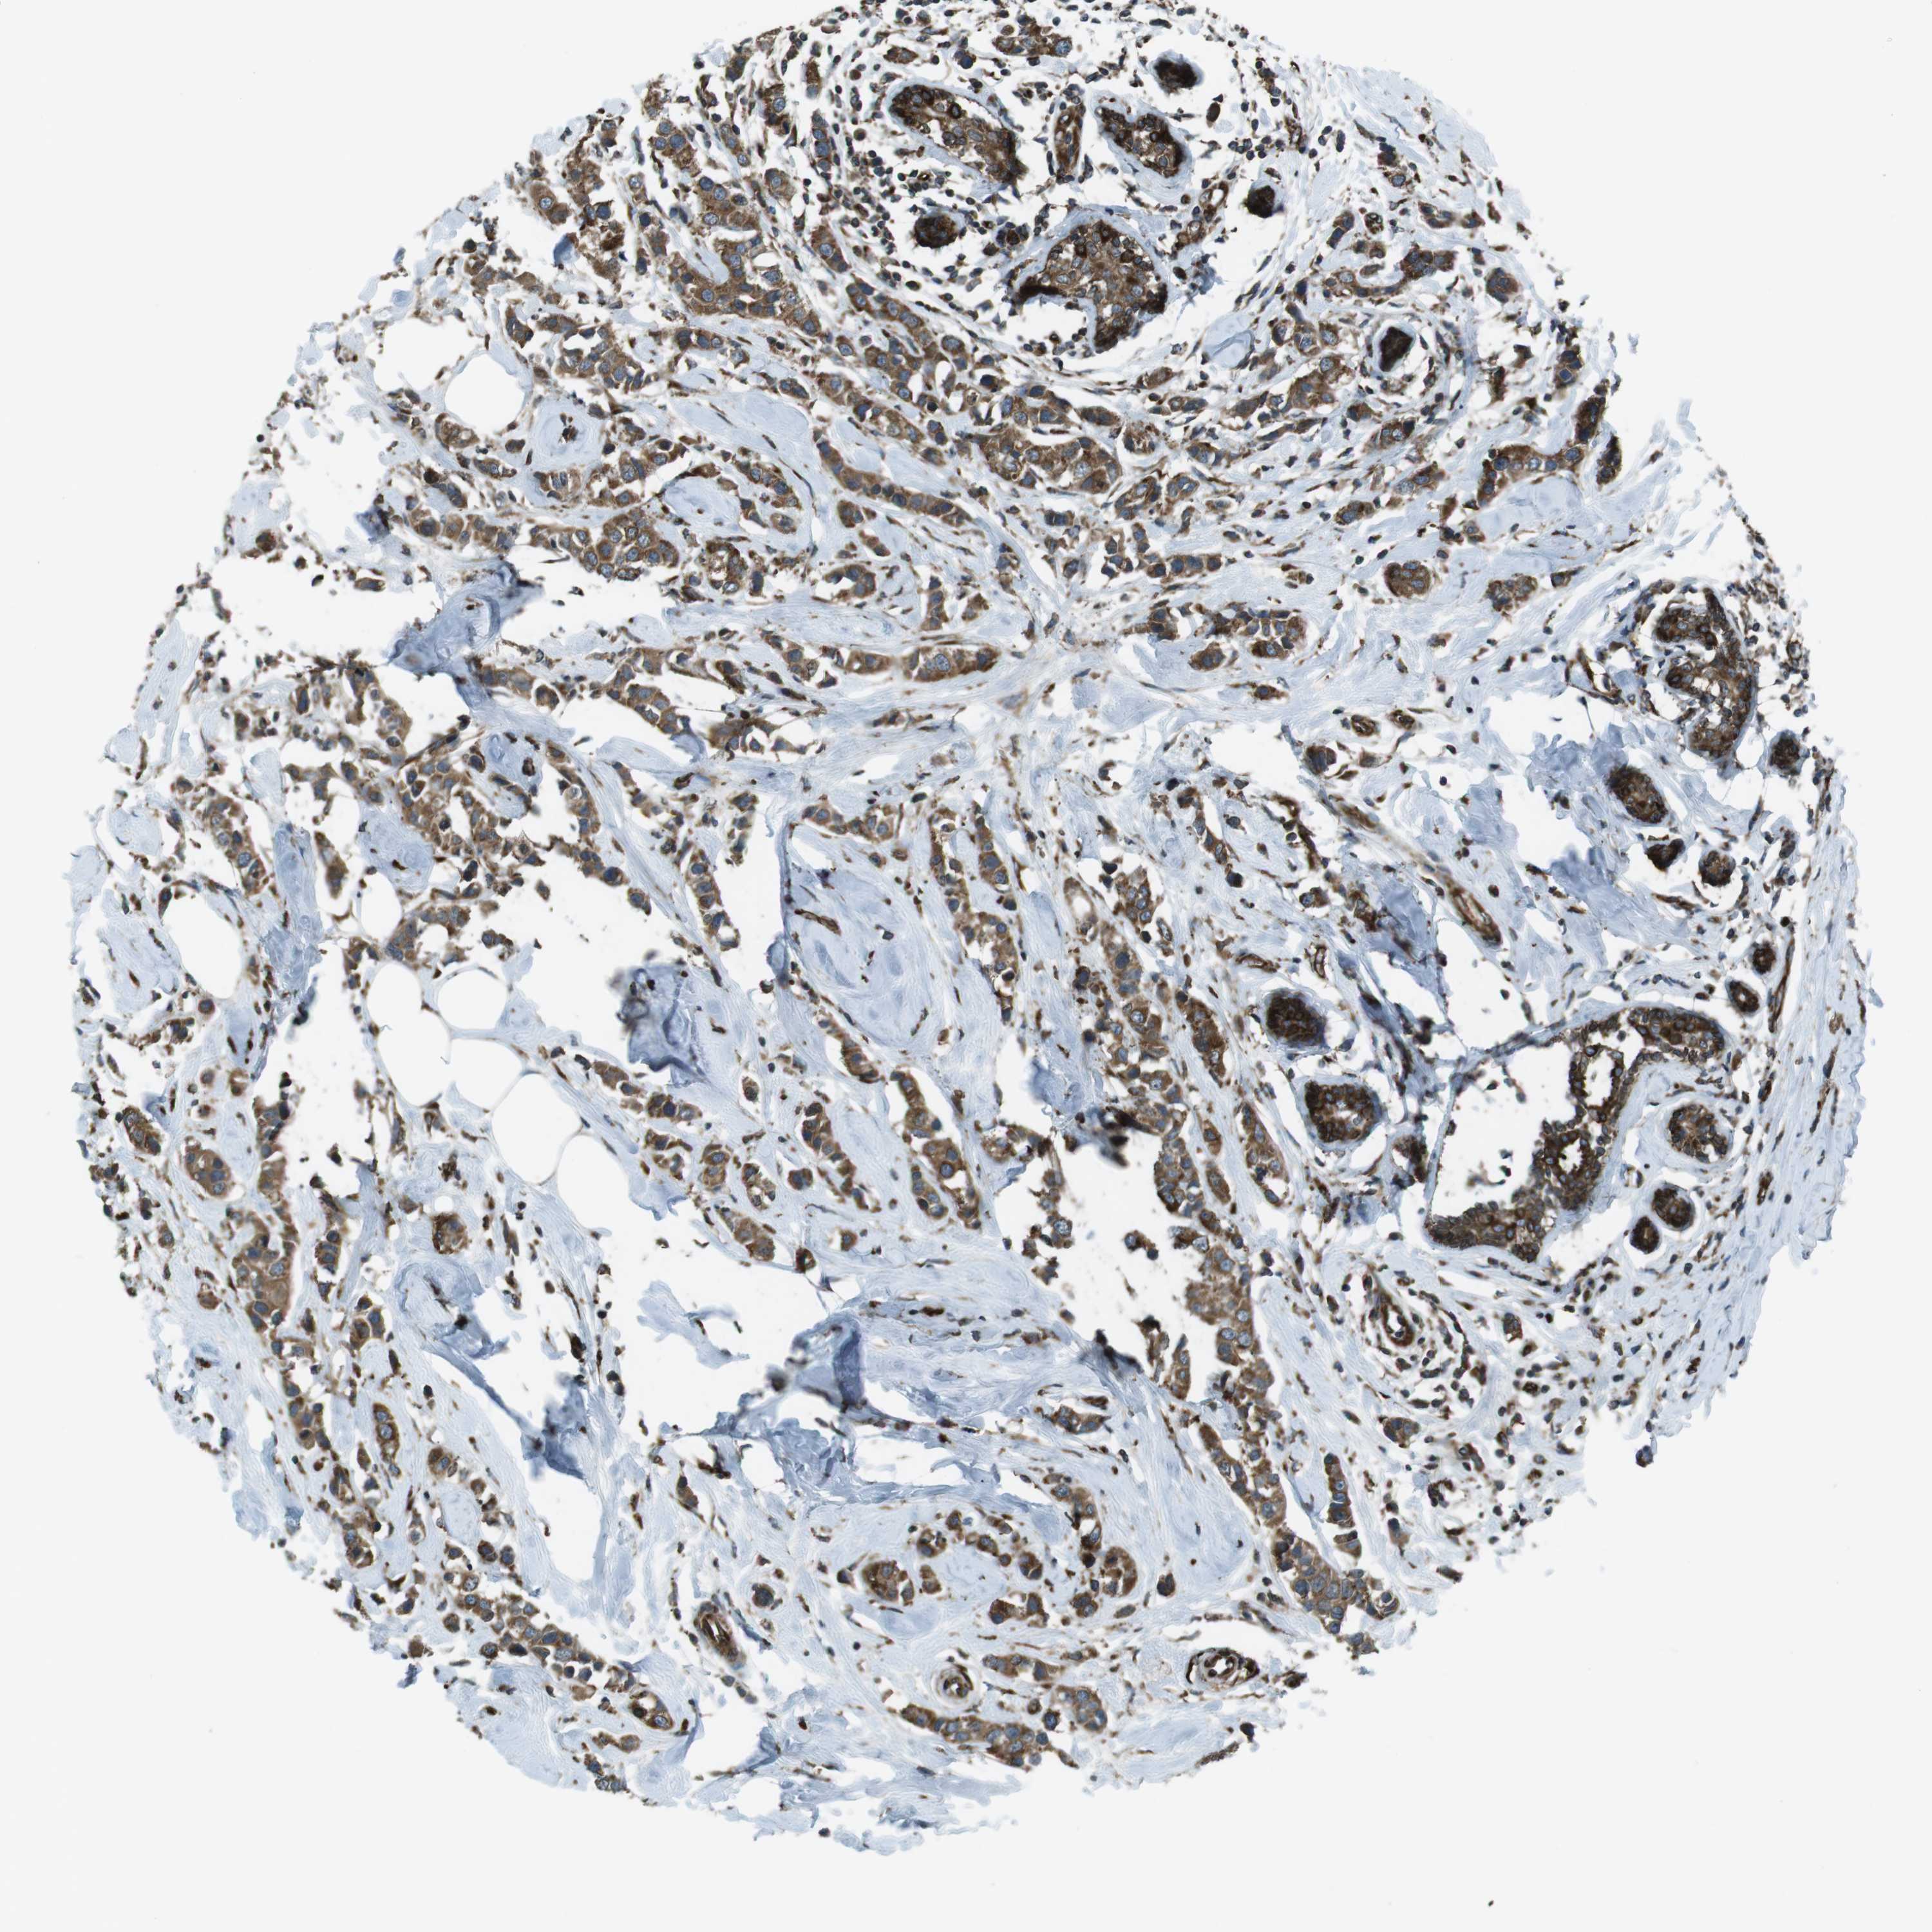

CANCER BREAST CANCER Show tissue menu

BRCA TCGA BRCA VALIDATION PROTEIN EXPRESSION